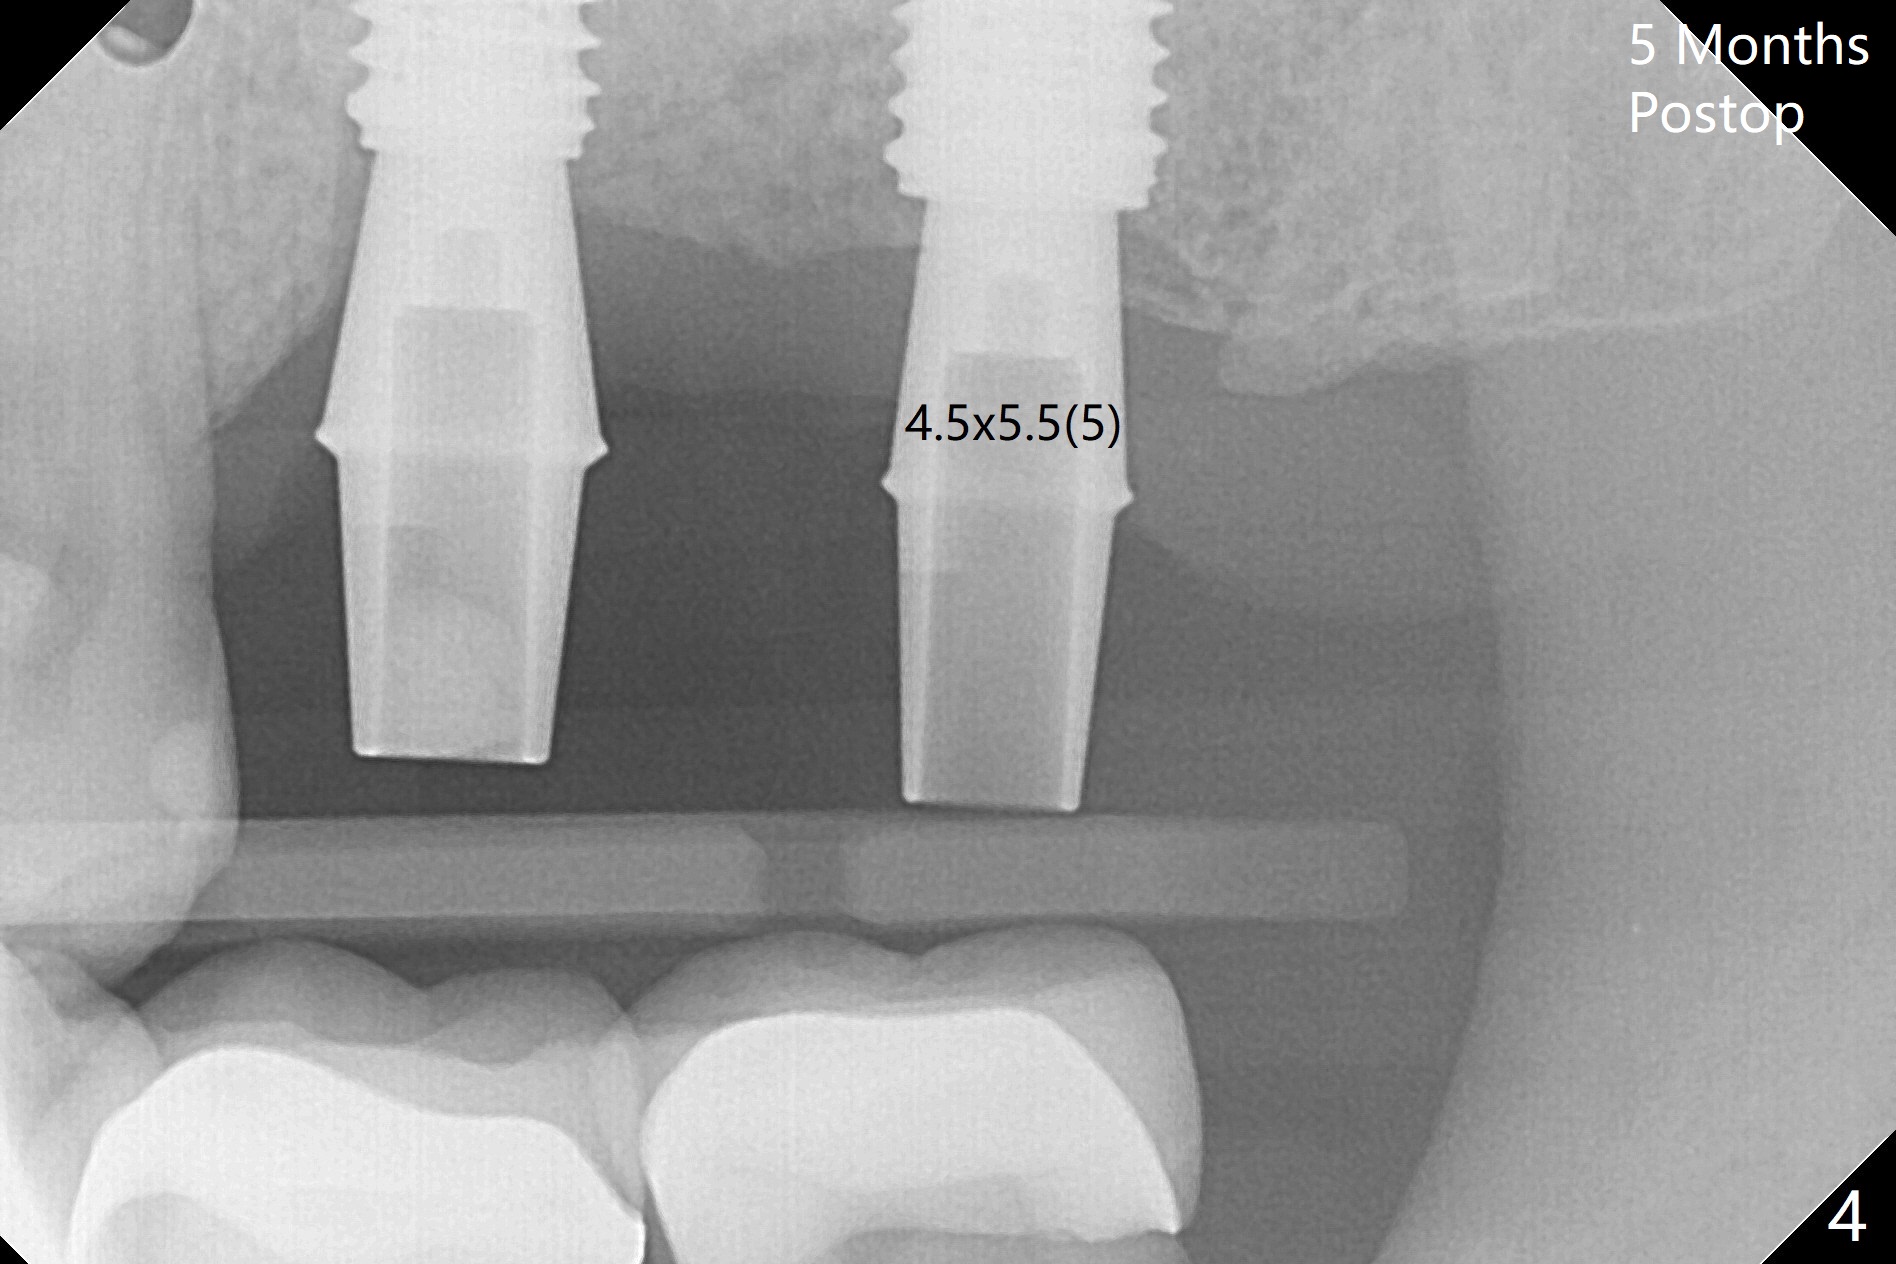

With one carpule of 2% Xylocaine with 1:100,000 Epinephrine, there is no intraop pain associated with placement of 2 implants with guide (Fig.1). Postop pain is minimal. Difficulty is high torque in insertion. At the site of #15, there is no bone shaving associated with 4 mm or less drills. The deeper portion of the bone seems to have denser bone. In spite of using 5 mm tap, which is not recommended, the insertion torque is so high that the implant has to be backed up several times before placement with ~ 50 Ncm. Bone profile is used at #14 before placement of a 5.5x7 mm healing abutment. The healing abutment at #15 dislodges 3 weeks postop and changes to a 5.5x5 mm one. No bone loss is observed 4 months postop (Fig.2). After failure to deliver crowns using impression coping, abutments are placed. The one at #15 is incompletely seated (Fig.3 <) probably due to the contact with the distal crest (*). Change to a smaller one results in complete seating (Fig.4). Cementation of the crowns with access holes is related to no residual cement (Fig.5).